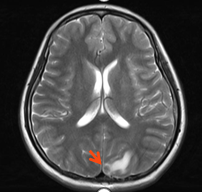

1.乳腺增强MRI:左侧乳腺多发肿块,形态不规则呈分叶状,边缘毛刺,内部呈不均匀混杂强化,病灶最大直径约7.2cm(靶病灶1)。(图1)

图1. 乳腺增强MRI

1.靶病灶1(乳腺原发病灶)评效:2周期部分缓解PR,4-6周期乳腺病灶呈非肿块样强化,无法测量病灶大小,8周期复查无强化,疗效达CR。(图7)

图7 靶病灶1(乳腺原发病灶)评效CR